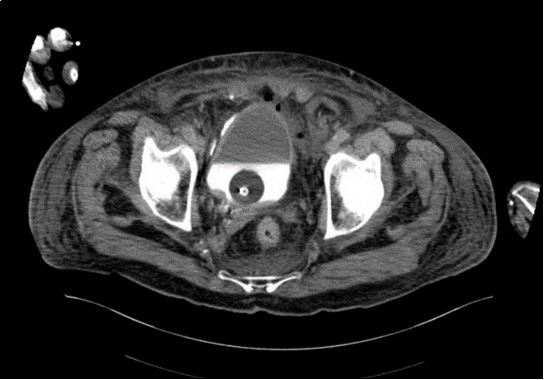

An urgent CT abdomen revealed a bladder perforation with the tip of the irrigating catheter situated in the abdominal cavity (Figure 1, Figure 2, Figure 3a,Figure 3b). This was most likely due to over-insertion of the 3-way catheter due to the extra force required because of the benign prostatic hypertrophy. He had therefore been receiving normal saline as ‘peritoneal dialysis’ with normal saline since insertion of the catheter. The catheter was withdrawn, and the patient made a full recovery.

Figure 3b.horizontal plane CT image

horizontal plane CT image